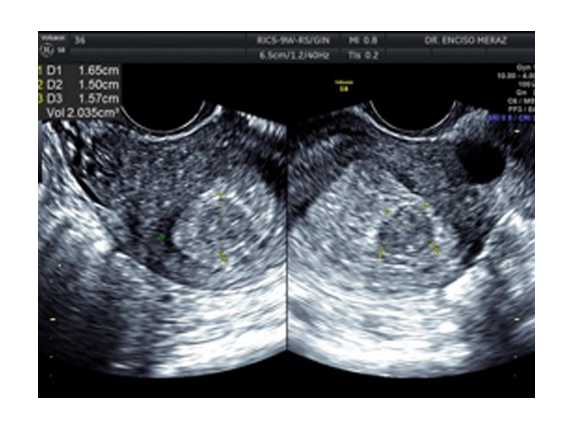

MIOMATOSIS

Leiomiomatosis, son los tumores benignos uterinos mas frecuentes de la mujer.

Se originan de las celulas musculares del utero. Tienen una frecuencia del 30% de todas las mujeres, estando con mayor frecuencia en la decada de los 30 y 40 años.